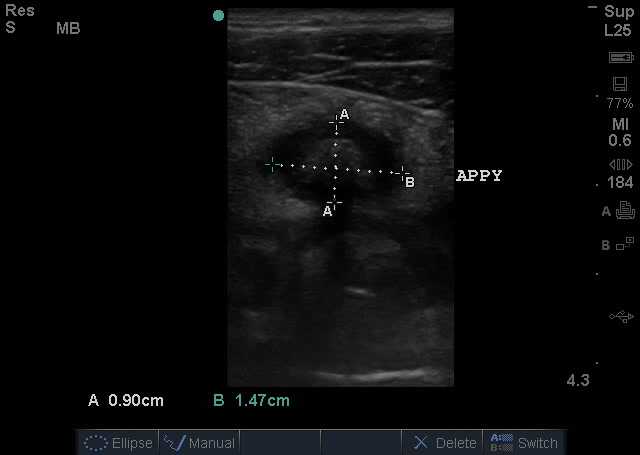

Ok, back to the case reports in WestJEM by Bramante et al. The 2 cases showed the evaluation and pretty obvious sonographic images seen with acute appendicitis with transvaginal ultrasound after an equivocal transabdominal ultrasound:

Screen Shot 2014-05-23 at 1.38.05 PM Screen Shot 2014-05-23 at 1.38.12 PM

Now, to review, appendicitis is diagnosed by applying the linear (or curvilinear if added depth is needed) probe to the area where the patient points to noting maximal pain, with the indicator toward the patient’s right side. Graded compression is then performed in that region which should displace and flatten bowel, identifying the psoas muscle and the transverse view of the iliac vessels. The appendix usually is located just anterior to these structures coming off of the cecum, and is normally compressible without being more than 6mm in diameter. It may be in its transverse or longitudinal view depending on anatomy. The entire appendix should be viewed, including to its tip. Be sure to view it in two orthogonal planes (rotate probe 90 degrees) to ensure it is the appendix, as a lymph node may look very similar to a transverse appendix but will not elongate into a tubular structure when viewed in its longitudinal plane. Here are some views of a positive appendicitis (absence of compressibility with attempts, dilated appendix):

APPENDICITIS WITH MEASUREMENTS_crop

Appendicitis by Ultrasound: A greater than 6mm in diameter, aperistaltic, non-compressible appendix +/- appendecolith.